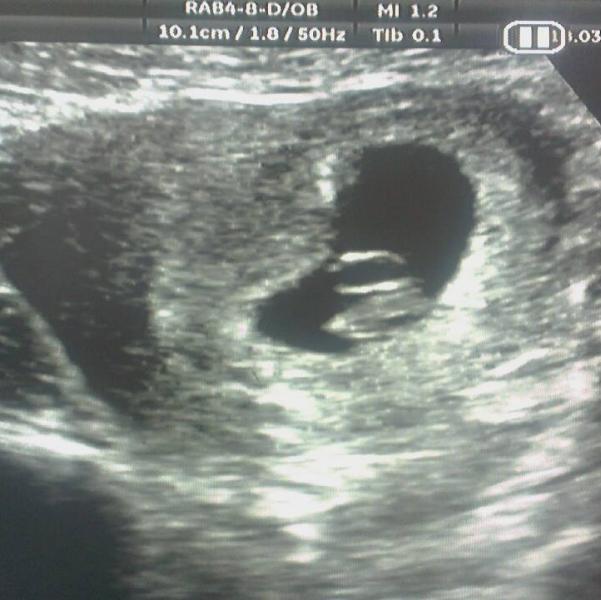

didn't know I could do the ramzi method this young but here we go.... any luck on guessing??? I was 7 week's 4 day's at this point, thought I was 8+ week's but they put me back few day's (gutted but glad my rainbow baba there) so if anyone can see anything he interested to know. I have this on disc so that's why there is a pause symbol top corner. can't wait till my 12 weeks(hope they see something due to being put back some day's!) scan and they can give me a an actual scan I can hold. have more so if you need to see them will post them in comments as can only put 1 up :-(

@darciepenny, ooh tiny wee bean so cute ,just mad how they go from a wee seed to a big baby I love this being pregnant I really do(maybe its the no morning sickness haha) a girl that be awesome, I'm happy either way but I'm so hopeful for a wee girlie xx

thanks @winterbaby95 just looks like a wee bean to me hehe. soooo looking forward to my NHS scan I'm April, will defiantly be posting that. xx